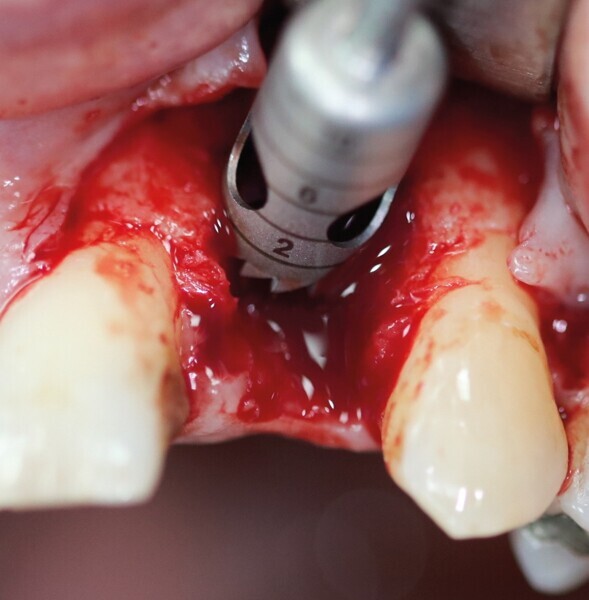

Après extraction de la première prémolaire maxillaire fracturée (Fig. 1), le soulèvement d’un lambeau a mis en évidence une perte osseuse vestibulaire sur toute la hauteur de la racine (Fig. 2). Cette lésion en « V » est rendue circulaire par un trépan de diamètre 5 mm (Fig. 3). Cela correspond au calibrage du défaut (Fig. 4). Le site d’extraction est parfaitement cureté. Le forage implantaire est réalisé contre la corticale palatine de l’alvéole d’extraction, au-delà de l’apex, pour permettre l’ancrage du futur implant. Le placement tridimensionnel de celui-ci est primordial par rapport aux collets anatomiques des dents adjacentes, ainsi que dans le sens mésio-distal et vestibulopalatin.3

Il ne faut surtout pas être piégé par la hauteur d’os perdu et enfouir plus l’implant. Un tissue level est parfaitement stabilisé grâce à ses dernières spires. (Implant TL Straumann SP 4,1 RN, longueur 12 mm SLActive). Une incision limitée en étendue et en forme de « H » est réalisée dans le secteur de la dent de sagesse inférieure, pour un abord crestal. Un trépan de diamètre supérieur au trépan de calibrage (Fig. 5), donc 6 mm dans ce cas, permet de prélever une carotte de 4 mm de profondeur (Fig. 6). Elle forme un bloc circulaire cortico-spongieux qui est impactée en force, transversalement à l’implant (Fig. 7). La surface SLActive de l’implant est au contact de l’os spongieux richement vascularisée et la partie corticale protège cet ensemble et referme parfaitement le défaut osseux (Fig. 8). L’os greffé est entouré par l’os du site receveur sur tout le pourtour. Son immobilité totale permettra sa consolidation et sa revascularisation.4 Il n’est pas utile d’enfouir l’implant ni d’utiliser une membrane, car il n’y a pas de substitut osseux (Fig. 9). La couronne définitive est réalisée à trois mois (Fig. 10). Le suivi de cette patiente montre un excellent comportement ostéo-gingival à dix ans, tant radiologiquement (Fig. 11), que cliniquement (Fig. 12).